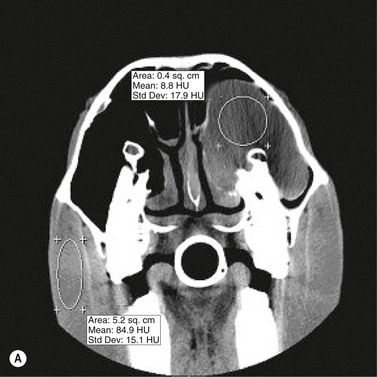

Technical principles

CT is a cross-sectional imaging method that uses a rotating X-ray tube and detector system located in a gantry for image acquisition. When the narrow X-ray beam passes through a selected plane of the body, it is partially absorbed when it passes through tissues with different attenuation coefficients (density). Each tissue is assigned a value that represents its attenuation coefficient. Computerized reconstruction programs are used to assign a gray scale value that correlates to the attenuation value of the tissue being imaged.32 Different algorithms can be used for image reconstructions.33 Each CT instrument manufacturer offers algorithms specifically designed for their individual hardware. For equine dental imaging, a soft tissue algorithm is useful for imaging of the soft tissue structures, followed by a reconstruction in a bone algorithm (high resolution) from the raw data, to allow detailed evaluation of dental and bony structures. The acquired sectional images can be reformatted in various two-dimensional planes or three-dimensional models (Fig. 13.51).

image image

Fig. 13.51 Three-dimensional reconstruction (A) of the bone surface image of an irregular depressed fracture involving the right frontal, nasal, lacrimal, and maxillary bones in a 5-year-old Friesian gelding. The location of fracture lines largely coincides with anatomical suture lines. The distribution and extent of these fractures are well highlighted in the 3D-reformation.